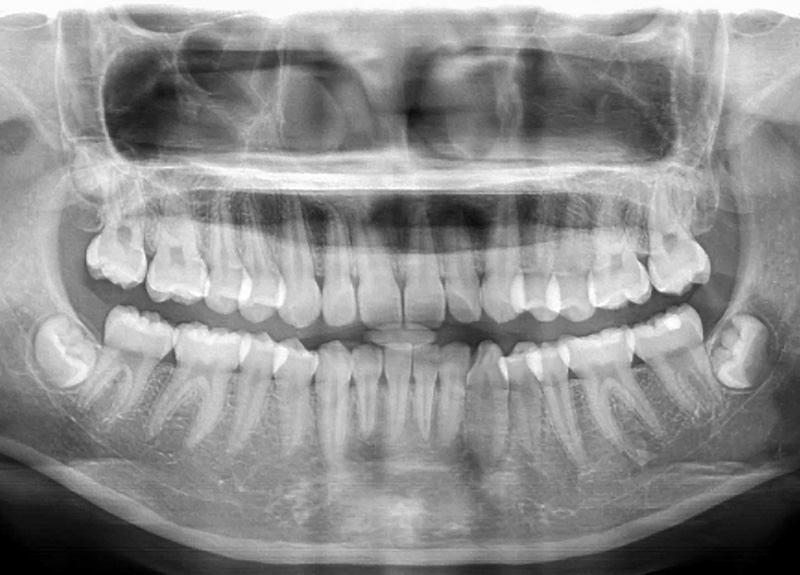

- パノラマX線

虫歯、歯周病、かみ合わせ、粘膜疾患等になっていないか、早期発見することを目的としています。必要に応じてレントゲン撮影を行い、歯磨きでは取りきれない歯垢や歯石を専用の道具を使用してクリーニングを行います。また、ご家庭でのケアのためのアドバイスを行います。

当院では、歯科ドックを通じて、皆様の口腔内の健康状態を総合的にチェックし、早期の問題発見・予防をサポートしています。定期的に歯科ドックを受けることで、むし歯や歯周、さらには全身の健康リスクを予防するために非常に重要です。